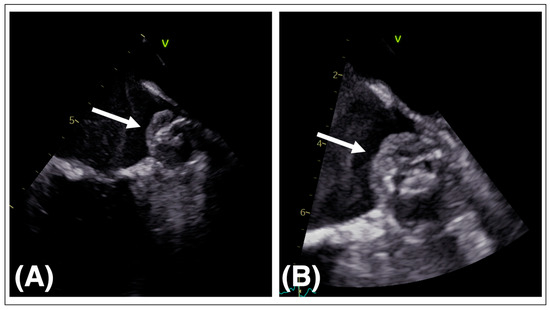

5.3. LAAO Device Embolization

5.4. Management of Device Embolization